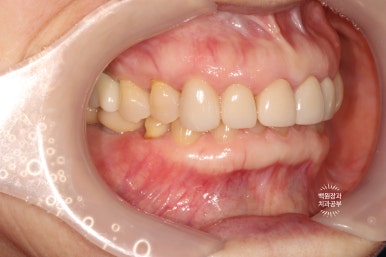

옆에서 보아도 너~무 잘 보이는 앞니 세로 금. 치아의 끝단에는 충치로 생각되는 어둑함이 자리잡고 있었고..

사진을 보시면 아시겠지만, 오른쪽 위 어금니 두개가 없으신 상태였습니다.

좌측과 우측 측면에서 보아도 아주 깔끔하게 유지되고 있는 앞니 지르코니아 크라운들입니다.

매우 흡족한 결과입니다 :)